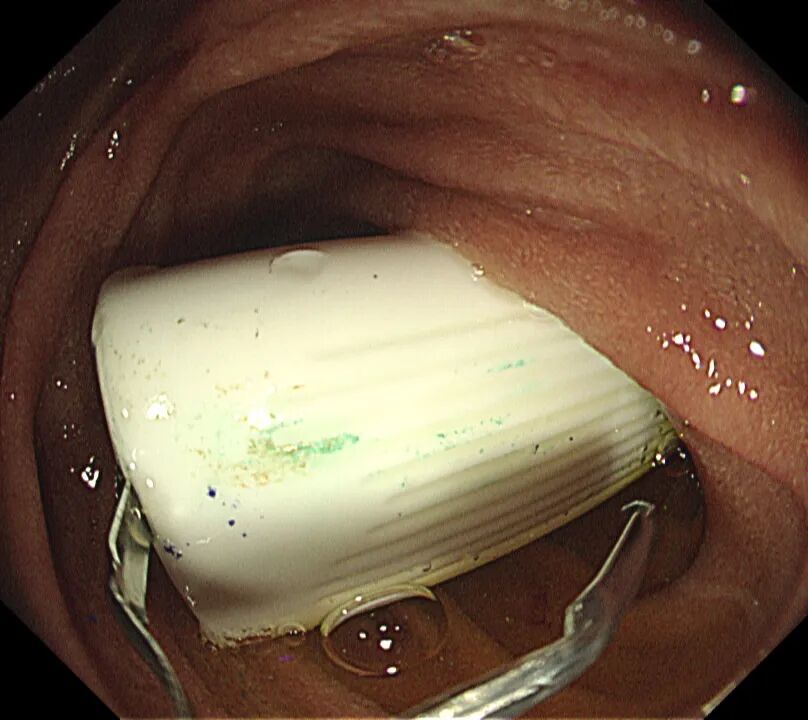

時(shí)間回到11月5日下午,楊先生6歲的孩子朗朗在上繪圖課時(shí),由于彩筆筆帽拔不掉,就用牙齒咬緊筆帽用力拔,拔下去的瞬間筆帽回彈正好被朗朗吞入,經(jīng)就近醫(yī)院診斷無(wú)法處理后,緊急轉(zhuǎn)入市二院就診。

經(jīng)醫(yī)生反復(fù)問診及觀察癥狀,判斷很大可能筆帽已進(jìn)入朗朗胃部或腸道。由于筆帽體積較大,開口端邊緣銳利,且由不透氣的塑料制成,如果滯留在胃腸道,可能引發(fā)腸梗阻、穿孔、黏膜損傷等嚴(yán)重風(fēng)險(xiǎn)。

時(shí)間不等人,雖已臨近晚7點(diǎn),市二院第一時(shí)間啟動(dòng)應(yīng)急響應(yīng)機(jī)制,內(nèi)鏡室、麻醉科醫(yī)護(hù)技立即返崗就位,并經(jīng)院辦等職能部門積極協(xié)調(diào),盡可能縮短術(shù)前準(zhǔn)備時(shí)間,迅速制定了取出異物的方案。隨后,在全身麻醉下,朗朗安然入睡,醫(yī)生通過纖細(xì)的胃鏡,精準(zhǔn)地找到了那個(gè)“惹事”的筆帽位于十二指腸內(nèi),并順利將其取出。整個(gè)過程僅用時(shí)十幾分鐘,朗朗術(shù)后很快蘇醒,觀察無(wú)礙后平安回家。